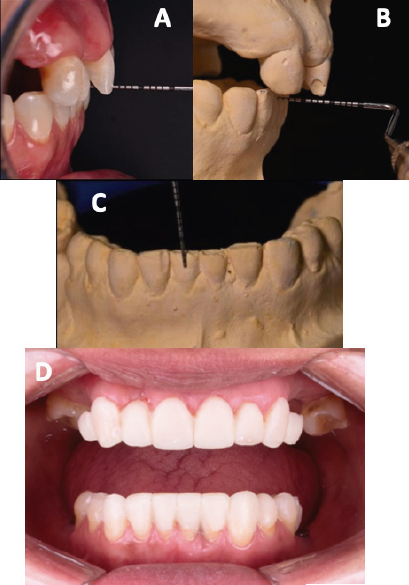

En el análisis oclusal presentó una sobremordida horizontal de 5mm en máxima intercupidación (Figura 2. B) y de 8mm en relación céntrica (Figura 2. C), discrepancia entre máxima intercuspidación y relación céntrica de 3mm, sobremordida vertical de 3mm (Figura 2. C) y un espacio libre interoclusal de 5mm. El objetivo del tratamiento fue la rehabilitación oral completa mediante el análisis estético, radiográfico, encerado, mock-up e intervenciones quirúrgicas pre protésicas para acondicionar la cavidad bucal y recibir los implantes y las restauraciones finales.

Figura 2 Análisis de sobremordida, mock-up y provisonal de acrilico. A. Sobremordida horizontal en máxima intercuspidación. B. Sobremordida horizontal en relación céntrica. C. Sobremordida vertical. D. Prueba de mock-up.

Una vez obtenidos los elementos de diagnóstico (modelos de estudio, radiografías y fotografías intraorales y extraorales), se procedió a realizar los análisis correspondientes, y con los modelos articulados en relación céntrica se elaboró un encerado de diagnóstico. Previo a la intervención periodontal, a partir del encerado de diagnóstico se elaboró un mock-up (Protemp™, 3M™) para establecer las proporciones dentales y los contornos gingivales deseados (Figura 2. D); de este modo se logró entablar comunicación con el periodoncista y tener los objetivos finales del tratamiento en común. El tratamiento se llevó a cabo en las cuatro fases:

En la Fase I se realizaron extracciones de los dientes 26 y 47, ya que presentaban un pronóstico periodontal sin esperanza. Se optó por mantener temporalmente los terceros molares superiores con el fin de utilizarlos como pilares para los provisionales. Los dientes 31 y 32 presentaban un pronóstico periodontal regular y pobre respectivamente, por lo que se decidió realizar una regeneración ósea en la zona interdental. Se colocaron implantes en los dientes 36, 46, se realizó la elevación de ambos senos maxilares y se colocaron implantes en los dientes14 y 16. En la Fase II, se prepararon los dientes de la arcada superior 13, 11, 21, 22, 23, se optó también por preparar y mantener temporalmente los terceros molares 18 y 28 para soportar un provisional de acrílico (AlikeTM, GC® America Inc) seccionado en hemiarcada de central a tercer molar, con refuerzo de estructura metálica (Figura 3. A). Se realizó de esta manera debido a los largos periodos de cicatrización que se presentarían durante el tratamiento, para evitar fracturas por la longitud de las brechas desdentadas y para mantener dimensión vertical. Se realizaron alargamientos de corona en los dientes 13, 11, 21, 22, 23 (Figura 3. B). Un mes después se re-prepararon los dientes para colocar el margen a nivel equigingival. Se tomó una impresión con alginato (Hydrogum 5, Zhermack® Dental) para realizar un nuevo encerado y un nuevo provisional de acrílico utilizando la misma estructura metálica del provisional anterior (Figura 3. C). En la arcada inferior se realizaron preparaciones horizontales para carillas en los dientes 31, 32, 33, 41, 42 y 43 con el fin de restituir el tejido dental perdido y lograr un contacto con los dientes superiores. Se colocó un provisional de resina bisacrílica (Protemp™, 3M™).

Figura 3 Provisional de acrílico y preparación de dientes. A. Refuerzo de estructura metálica de provisional acrílico. B. Dientes antes de preparar el margen gingival. C. Márgenes equigingivales, tres meses después de los alargamientos de corona.